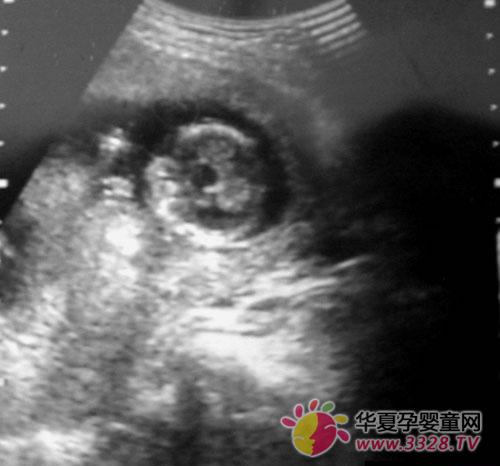

怀孕3个月胎儿b超图

b超图怎么看